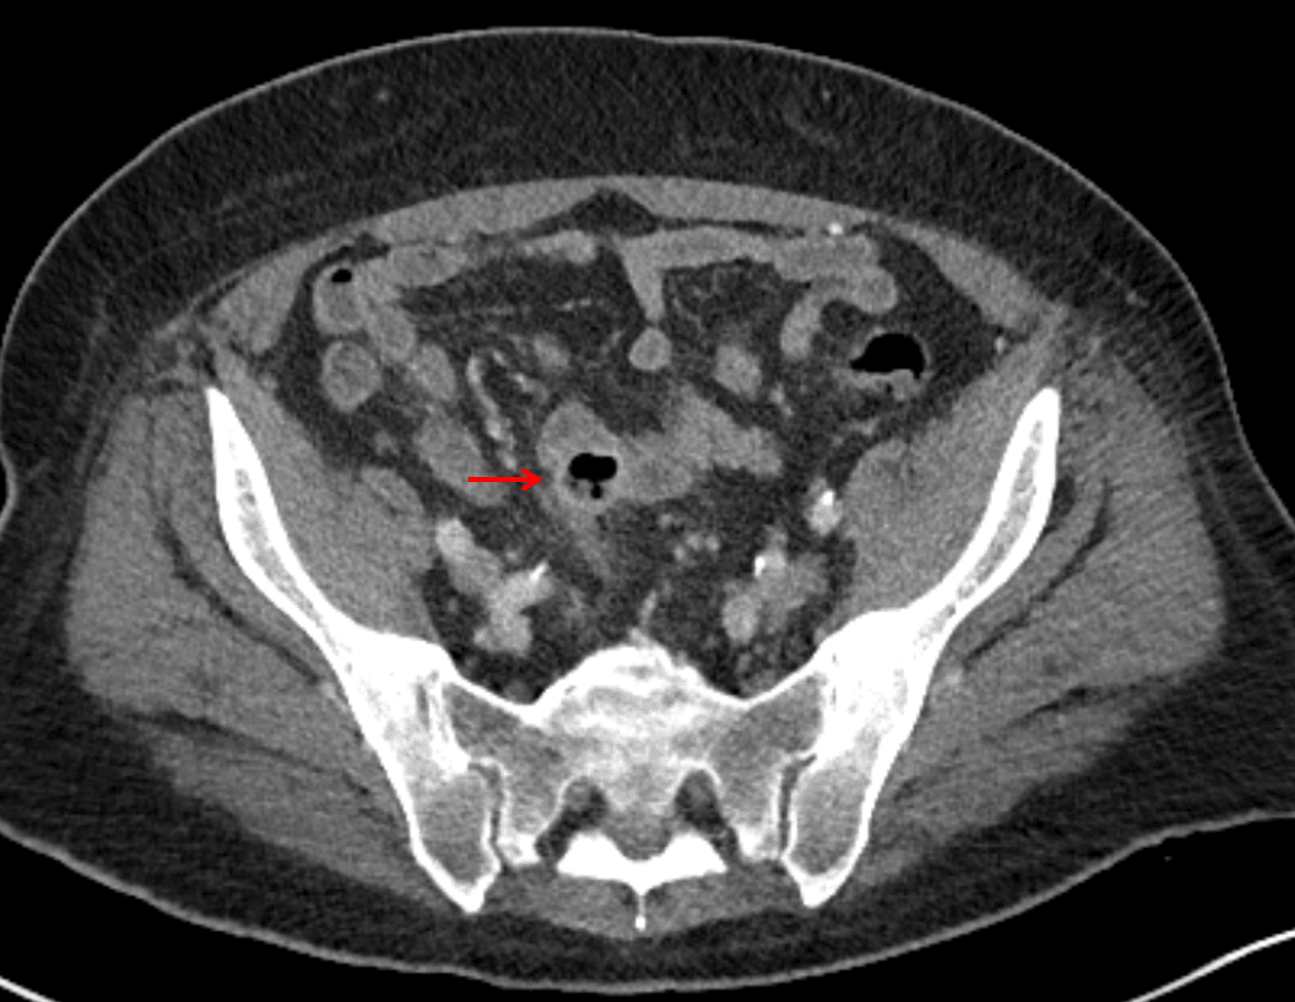

- Mild mural thickening of a segment of the sigmoid colon with adjacent fat stranding and a 1.5 cm fluid and gas collection along the tip of an inflamed diverticulum

- Loss of the normal fat plane between this collection and adjacent loops of small bowel, which demonstrate mural thickening

Additionally, there is loss of the normal fat plane between the peridiverticular collection and adjacent thickened loops of small bowel raises the potential for an enterocolonic fistula.

Red arrow: focal contained perforation associated with diverticulitis.